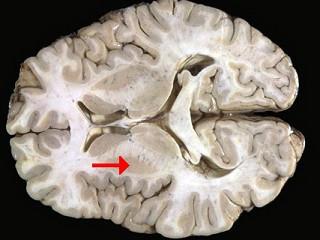

如图箭头所示为大脑哪个部位 ( )A、内囊B、齿状核C、丘脑D、尾状核E、壳核一、单项选择题

问题 如图箭头所示为大脑哪个部位 ( )

选项 A、内囊 B、齿状核 C、丘脑 D、尾状核 E、壳核 一、单项选择题

答案 E